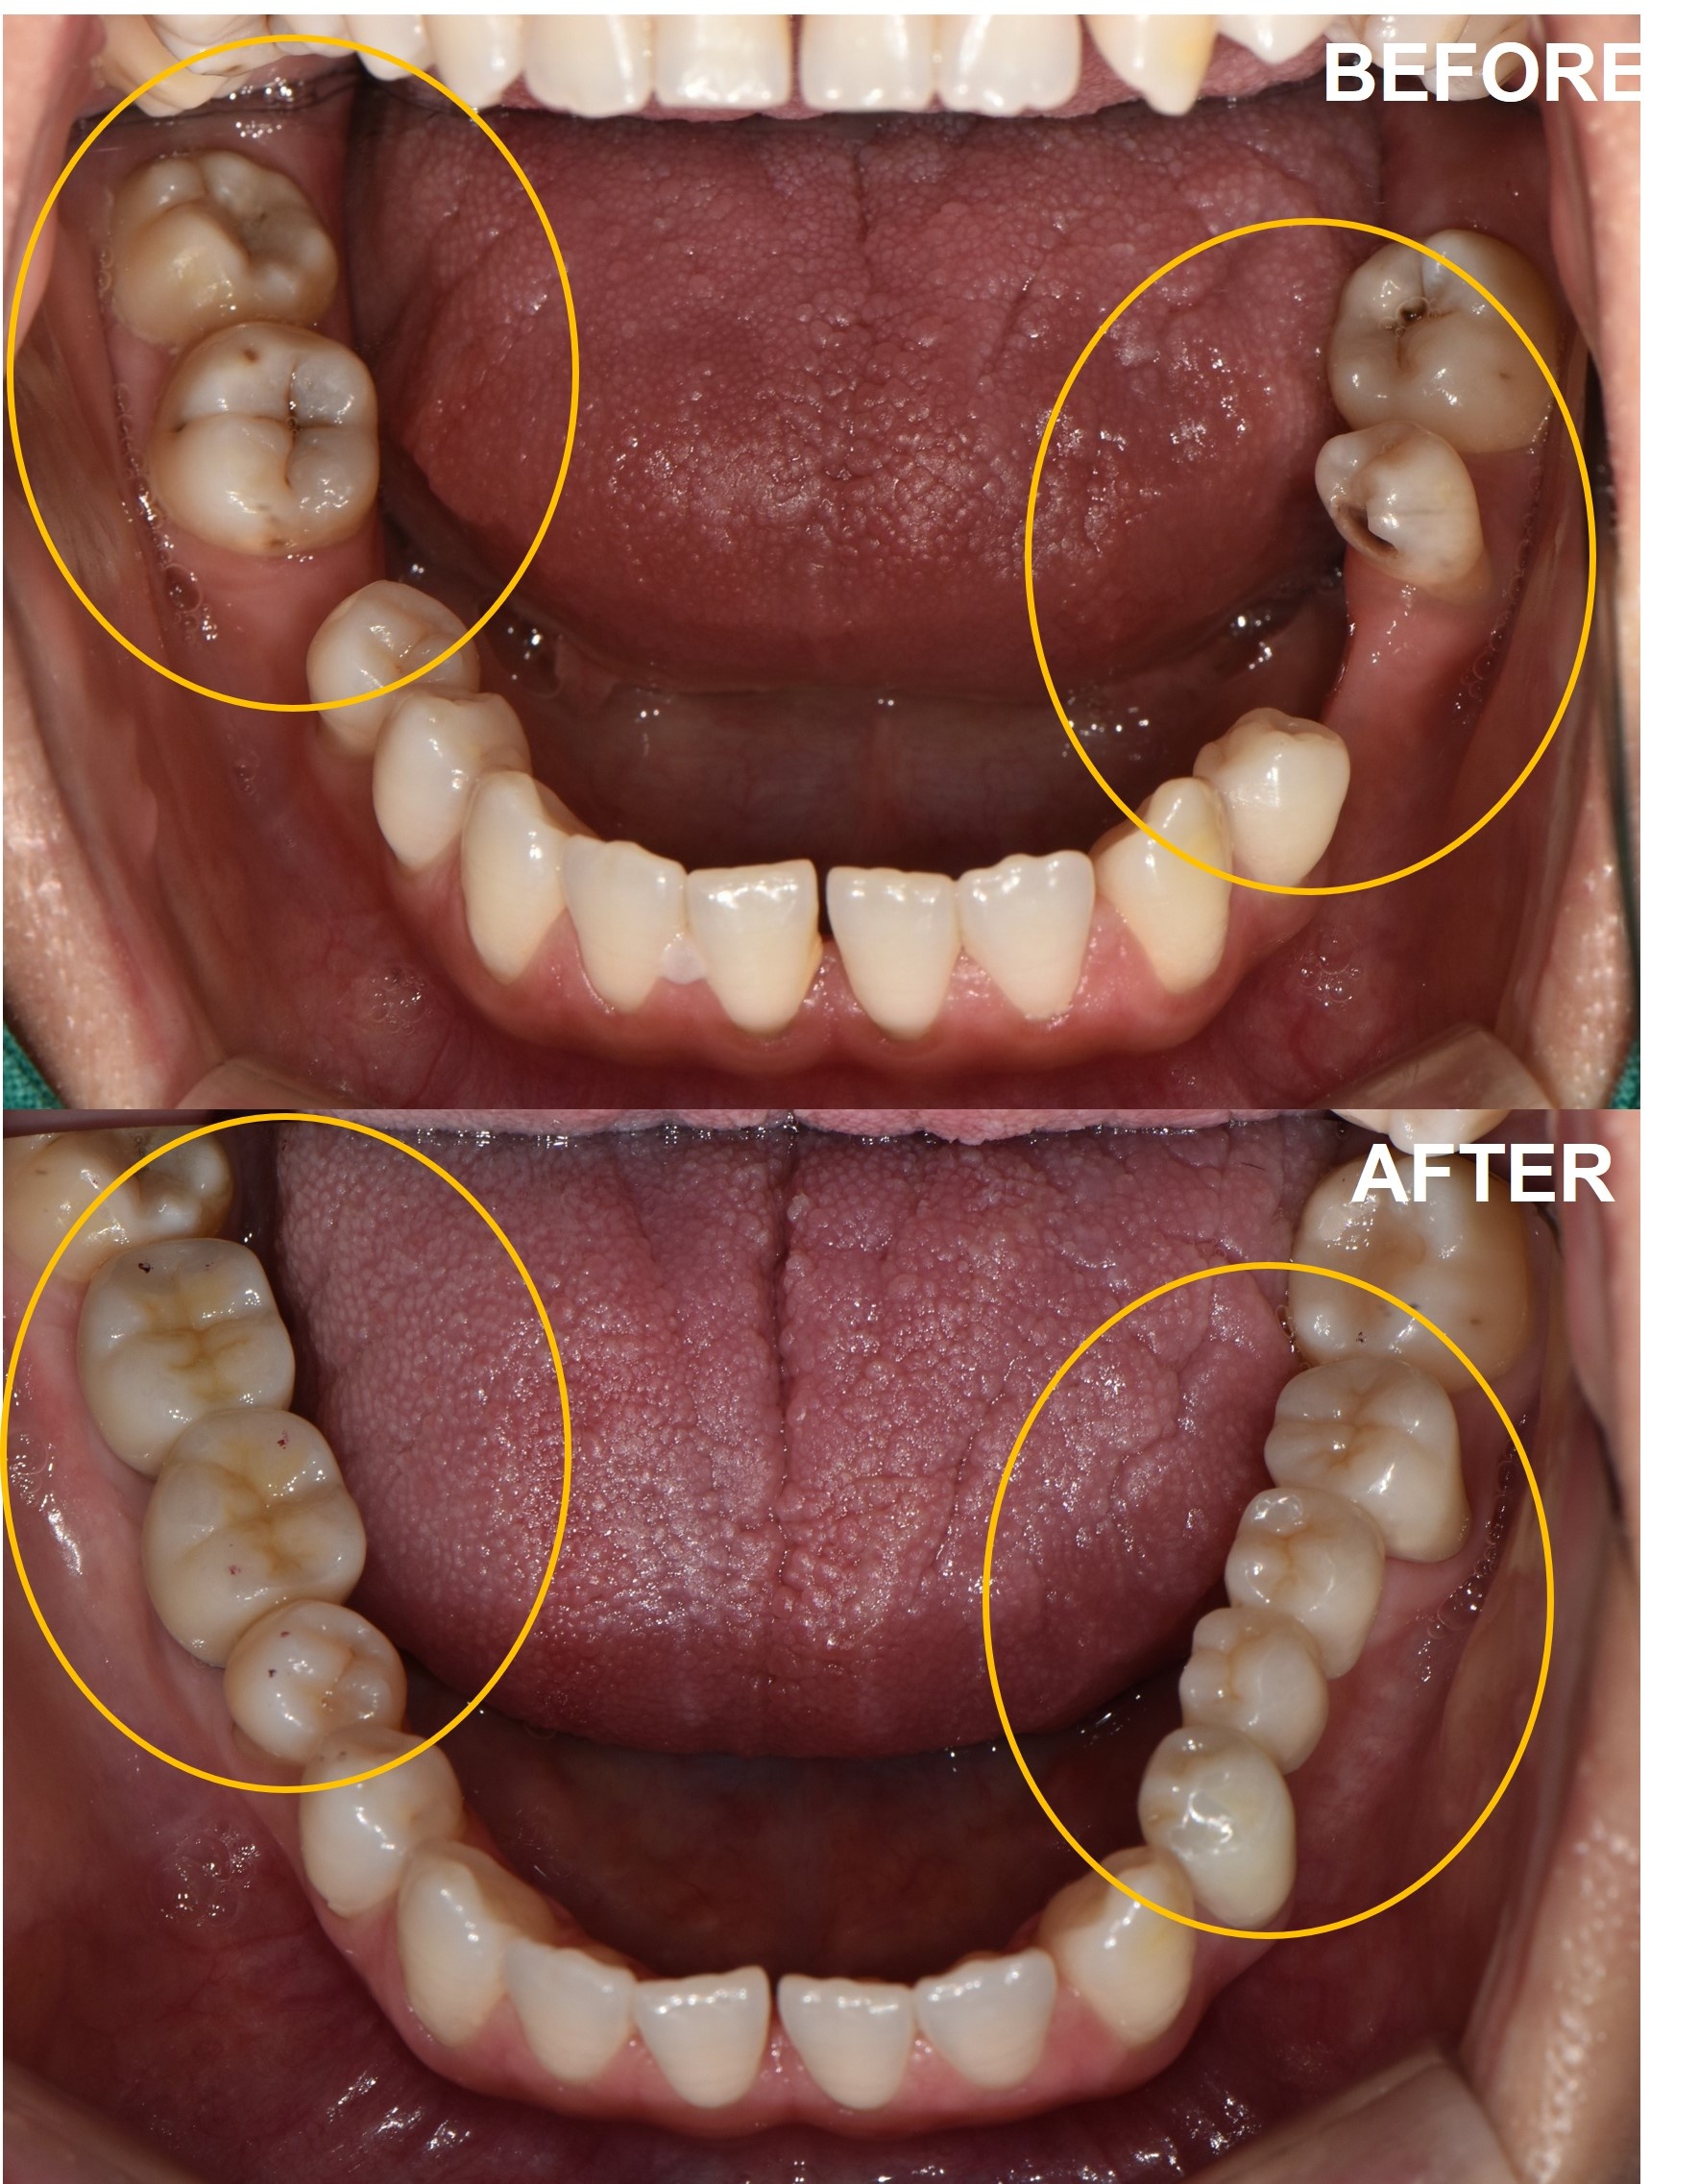

비포 사진과 애프터 사진을 나란히 놓고 보니, 단순히 치아가 생긴 것 이상의 변화가 보였습니다.

쏠렸던 치아들은 제자리로 돌아갔고, 교합 평면은 균형을 이루었으며, 양쪽 어금니가 동시에 닿으면서 턱관절의 부담도 줄어들었습니다.

2023년 1월부터 시작된 치료는 총 4개의 임플란트 식립과 브릿지 제작, 그리고 교합 조정 과정을 거쳐 7월까지 약 6개월간 진행되었습니다.